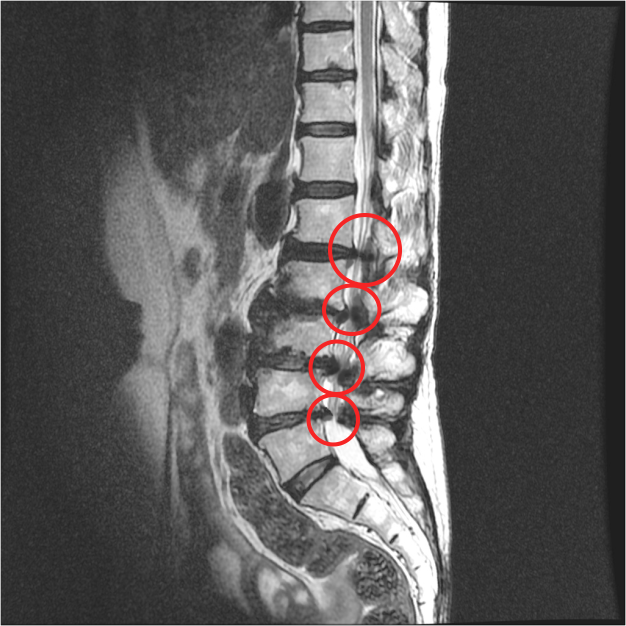

② 척추관 협착증

30대 이후부터 척추의 퇴행성 변화가 시작되면서 척추 뼈 사이 공간이 점차 좁아지는 질환입니다. 뼈의 퇴행으로 인해 골극(가시 같은 모양으로 튀어나온 뼈)이 생기고, 주변 인대가 두꺼워져 척추관이 4방향에서 압박됩니다. 결과적으로 척수와 신경근이 눌리면서 다리 저림, 당기는 증상, 장거리 보행 시 통증이 나타납니다.